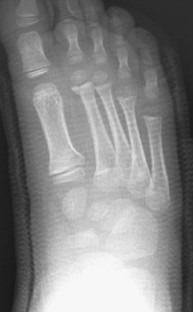

Fig. 1